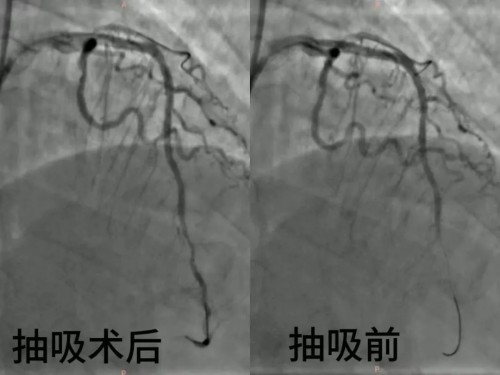

医院心血管(肾内)科介入团队迅速启动急诊介入手术流程。术中,团队凭借精湛的技术和丰富的经验,精准定位血栓位置,仅用15分钟便顺利完成血栓抽吸操作。随后,为患者置入1枚支架。术后复查显示,患者未留下明显心功能损伤,手术取得了圆满成功。

急性心肌梗死发作时,冠状动脉会在破裂斑块的基础上,瞬间被血栓堵塞,心肌细胞随即在缺血缺氧中迅速走向坏死,其核心症结,正是血栓堵塞冠状动脉。当血栓负荷量较大,单纯依靠球囊扩张难以有效清除血栓,此时,血栓抽吸治疗便成为关键手段。这一治疗方式宛如为血管聘请了一位专属“清道夫”。治疗过程中,医生借助血管造影精准定位血栓位置,将纤细的抽吸导管沿血管路径轻柔送达闭塞处。整个操作在影像引导下精准可控,最大程度避免了对血管壁造成额外损伤。合理应用血栓抽吸技术,能够更快速地恢复冠脉血流,缩短心肌缺血时间,有效预防远端血管栓塞,最大程度保留心肌功能,降低心衰、心律失常等远期并发症的发生风险。